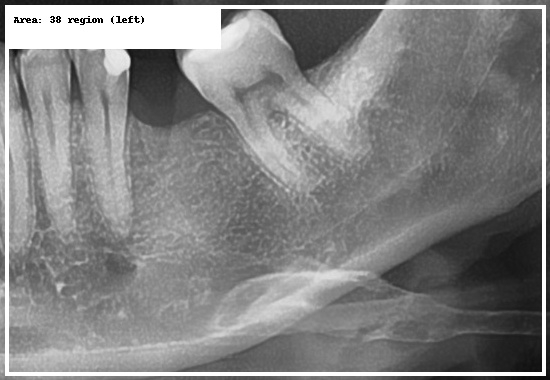

RTG zęba (punktowe) – szybka diagnostyka bólu i próchnicy

RTG punktowe (zębowe) to precyzyjne badanie 1–2 zębów. Sprawdza się w diagnostyce bólu,

wykrywaniu zmian okołowierzchołkowych, próchnicy międzyzębowej oraz w kontroli

leczenia kanałowego pod mikroskopem.

Jeśli boli konkretny ząb i szukasz miejsca na rentgen zęba Łódź, zwykle zaczynamy właśnie od RTG punktowego.